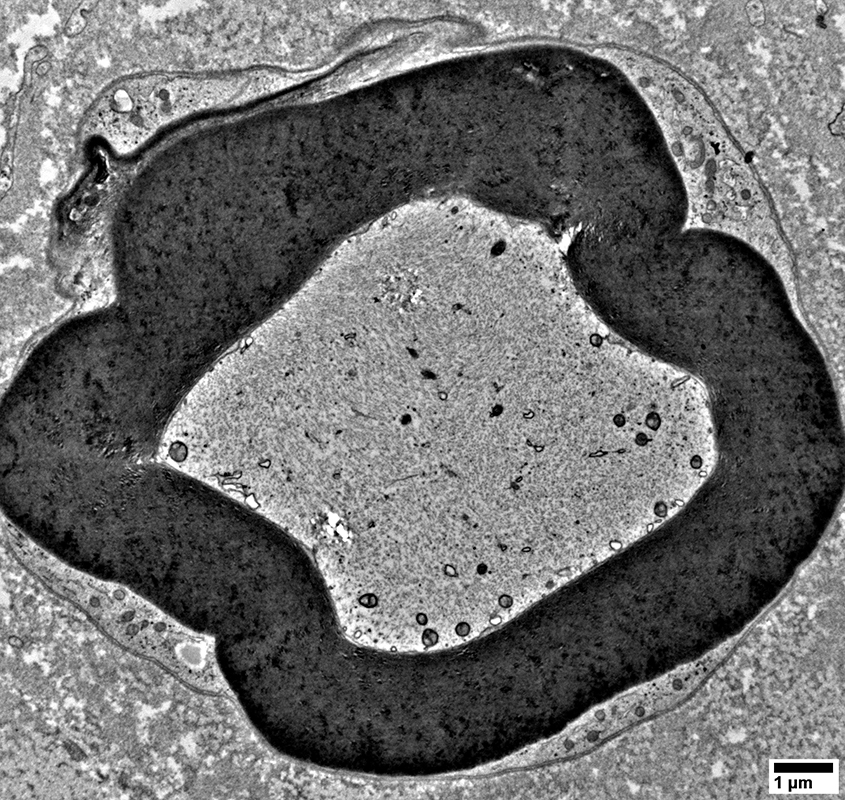

Axons surronded by layers of Schwann cell processes

From: R Schmidt